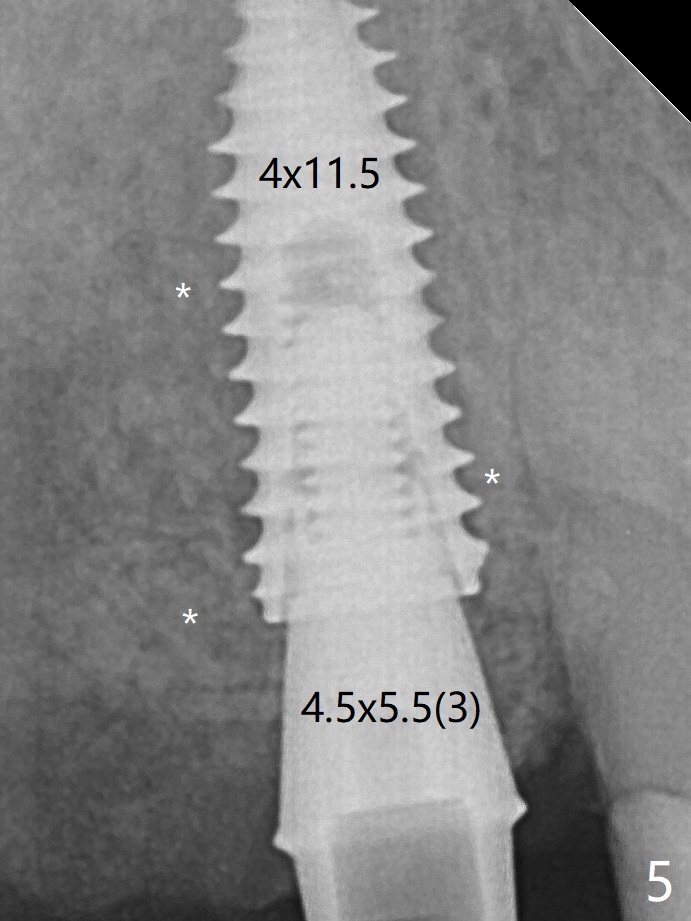

Once an abutment is placed at #5 (Fig.2 A, 5) for temporary crown (Fig.4 T) , the guide may be not seated again unless the crown is removed. Allograft (*) not only covers the exposed implant threads, but also the denuded root surface of the canine.  The implant seems to be covered by the bone 4 months postop (Fig.7).  In fact the abutment has not been seated completely.